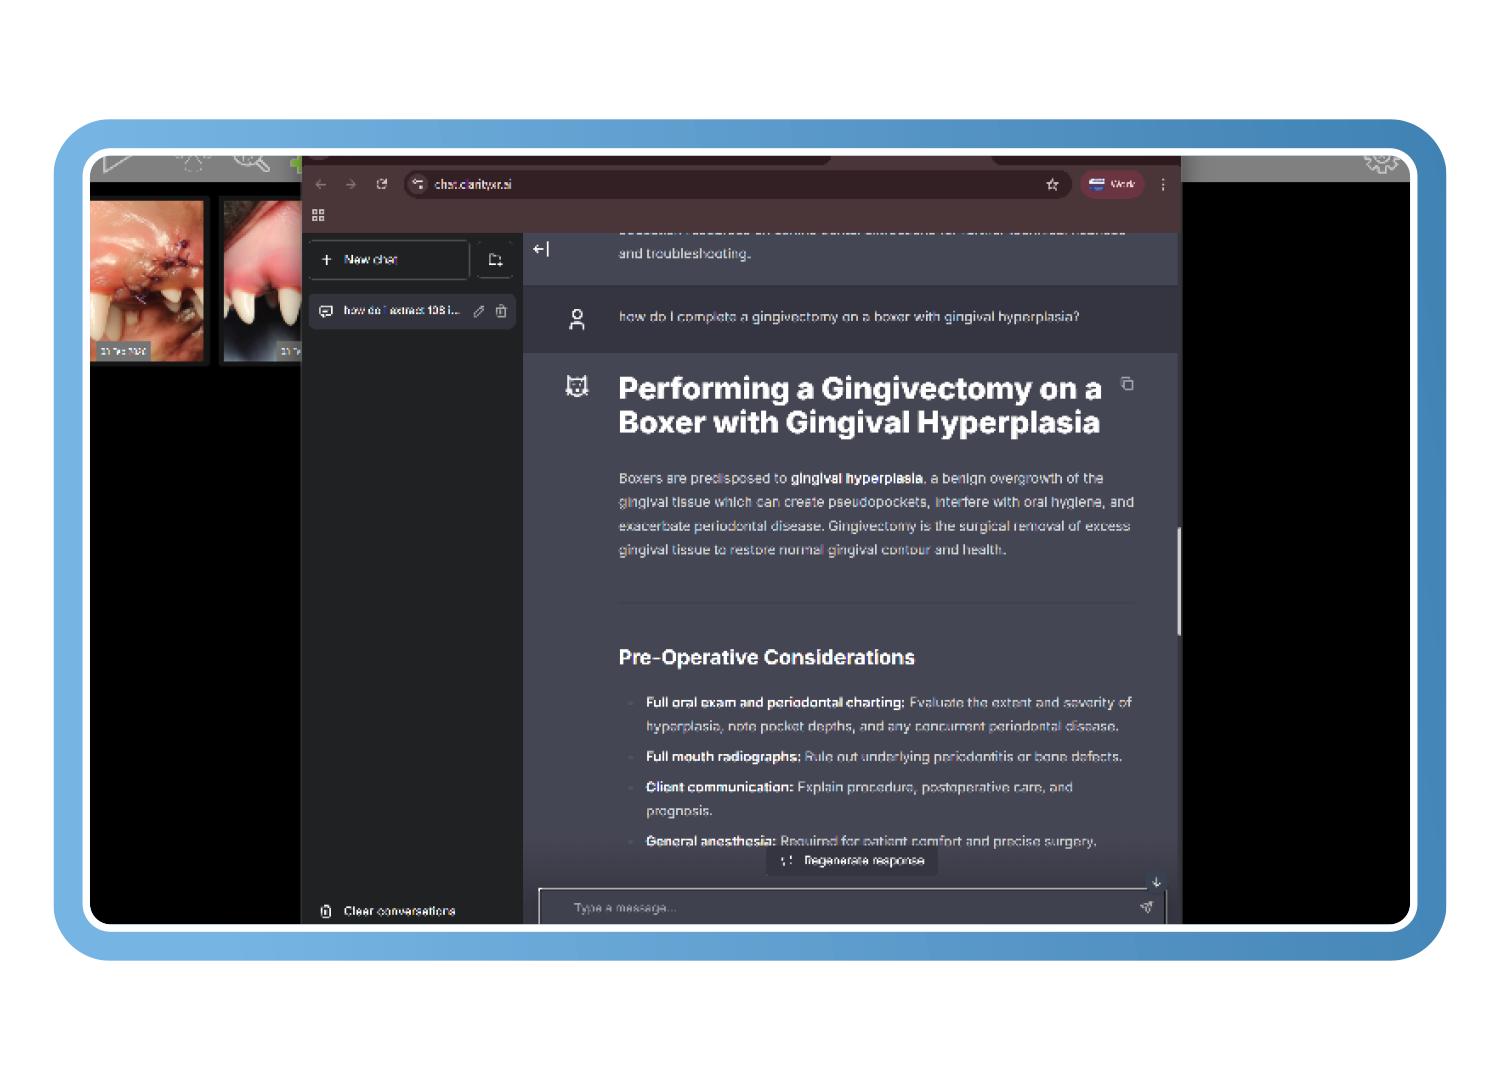

Clarity Question Lab (Aprendizaje y orientación clínica)

El laboratorio de preguntas de Clarity responde a cuestiones clínicas y procedimentales utilizando las directrices dentales de la WSAVA y material revisado por pares de especialistas en odontología veterinaria certificados por el consejo.

Las explicaciones instantáneas paso a paso respaldan el aprendizaje clínico y la coherencia, convirtiendo los casos cotidianos en momentos de enseñanza guiados según las mejores prácticas.